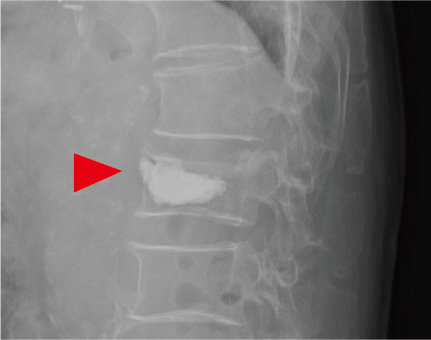

最近、BKP(balloon kyphoplasty)やVBS(vertebral body stenting)といわれる、椎体内にバルーンを膨らませて、セメントを詰めたり、ステントを留置してその中にセメントを詰める治療ができるようになりました(図1)。ともに、全身麻酔が必要ではありますが、傷は正中から約2cm離れたところにそれぞれ、5mm程度の傷で、手術自体は40分程度の短時間でできる手術になります。手術直後より劇的に痛みが軽減し、安静期間が短くなり、早期に離床することが可能となりました。しかし、BKP、VBSを行った後に、隣接椎体の骨折をきたす例が10~20%、詰めた椎体がさらに圧潰するのも約10%に認められます。これらの問題点を解消させるためにも手術施行後の骨粗しょう症の治療を継続して行うことが重要であると考えています。

当院にてBKPを行った症例の半数以上の方は、過去に1ヶ所以上の椎体骨折をすでに起こしており、圧迫骨折を2ヶ所以上起こしている方は、骨折リスクの高い骨粗しょう症と診断され、積極的に骨形成促進薬を使っていくことで、固定隣接椎体の骨折や、セメントを詰めた骨のさらなる圧潰が防げるものと考えています。圧迫骨折を起こした方は、積極的に骨密度を測定して、背骨の変形を防ぎましょう。